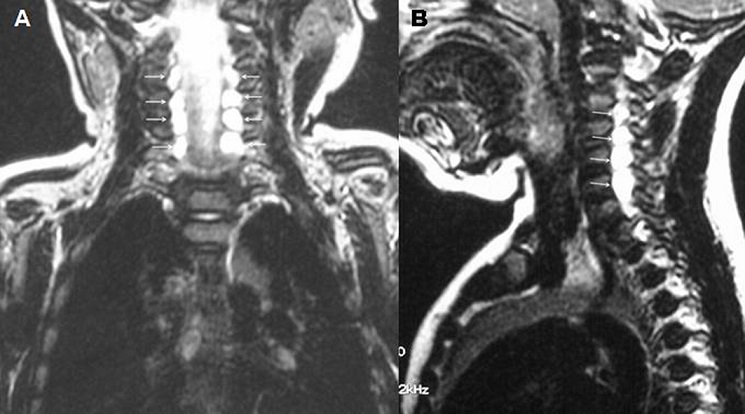

La paralysie obstétricale du plexus brachial est la plus fréquente des traumatismes obstétricaux. Elle reste une complication obstétricale redoutée qui doit faire l'objet d'un suivi particulier car elle engage le pronostic fonctionnel du membre. Sa fréquence varie de 0,42 à 5,1 cas pour 1000 naissances vivantes. La paralysie étant unilatérale, le diagnostic est souvent évident à la naissance après un accouchement laborieux. Le membre supérieur présente une paralysie flasque. Il est hypotonique et ballant en contraste avec l'hypertonie en flexion physiologique du côté normal. Les formes bilatérales de la paralysie obstétricale du plexus brachial sont exceptionnelles (1 %) et s'observe presque exclusivement dans la présentation de siège. Le traitement repose sur la kinésithérapie et la chirurgie réparatrice nerveuse dans certains cas. Nous rapportons un cas rare de paralysie bilatérale obstétricale du plexus brachial. Il s'agissait d'un nourrisson âgé de 3 mois, issu d'un accouchement présentation de siège, adressé à l'unité de médecine physique pour un déficit moteur des deux membres supérieurs. L'examen montrait une paralysie du plexus brachial bilatérale type C5 C6 sans signes de gravité associés. Le reflexe de moro était pathologique des deux cotés ainsi que la manœuvre de Foulard. Après 3 mois de rééducation à raison de 3 séances par semaine, aucune récupération n'est observée au niveau du deltoïde ni au niveau du biceps brachial. L'électromyogramme confirmait la dénervation bilatérale au niveau de C5, C6 et C7. L'IRM du plexus brachial révélait des pseudo-méningocèles bilatérales des racines C5, C6 et C7, témoignant d'une section nerveuse bilatérale. Le nourrisson était adressé pour chirurgie nerveuse.